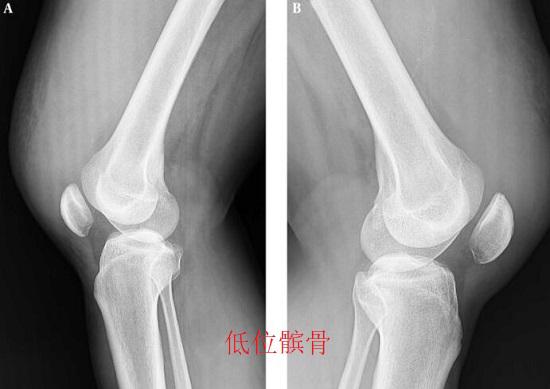

膝关节纤维化是指膝关节内因为瘢痕组织形成、纤维组织增生等原因出现关节腔变小、膝关节活动受限的一种病变。膝关节纤维化还是前交叉韧带重建术后最常见的并发症。在临床上,常将膝关节活动度缺失归结为“膝关节纤维化”。根据膝关节活动受限程度的不同,可将膝关节纤维化分为如下四个分型。I型膝关节纤维化比较轻微,只存在10度以下的膝关节伸展不足,以及少量的瘢痕和纤维化增生,有相当一部分的I型膝关节纤维化患者都可通过非手术方法获得恢复;II型的膝伸展度缺失大于10度,不存在屈曲障碍;III型在II型的基础上同时还存在25度以上的屈曲受限及髌骨活动受限,但不包括高位髌骨的情况;IV与III型在膝关节活动度方面相近,但将高位髌骨现象囊括在内。无论是哪个分型的膝关节纤维化,在非手段治疗效果有限的情况下,都可以考虑实施手术治疗。